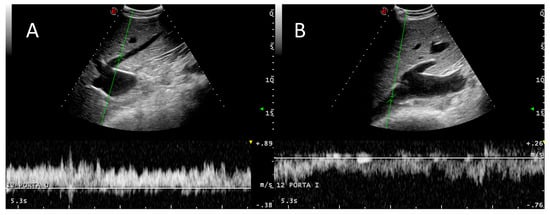

3.2. Portal System

3.3. Caudal Vena Cava and Hepatic Veins